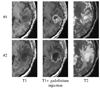

We propose a new model to simulate the three-dimensional (3-D) growth of glioblastomas multiforma (GBMs), the most aggressive glial tumors. The GBM speed of growth depends on the invaded tissue: faster in white than in gray matter, it is stopped by the dura or the ventricles. These different structures are introduced into the model using an atlas matching technique. The atlas includes both the segmentations of anatomical structures and diffusion information in white matter fibers. We use the finite element method (FEM) to simulate the invasion of the GBM in the brain parenchyma and its mechanical interaction with the invaded structures (mass effect). Depending on the considered tissue, the former effect is modeled with a reaction-diffusion or a Gompertz equation, while the latter is based on a linear elastic brain constitutive equation. In addition, we propose a new coupling equation taking into account the mechanical influence of the tumor cells on the invaded tissues. The tumor growth simulation is assessed by comparing the in-silico GBM growth with the real growth observed on two magnetic resonance images (MRIs) of a patient acquired with 6 mo difference. Results show the feasibility of this new conceptual approach and justifies its further evaluation.